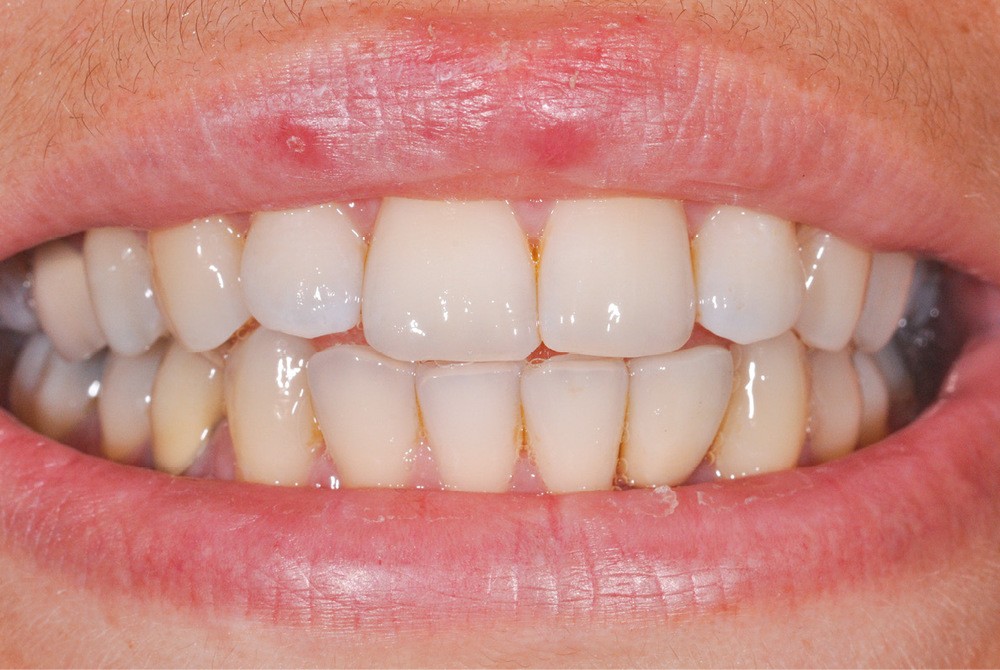

Le scellement de restaurations sur des piliers implantaires demeure une solution très intéressante (fig. 1). Cette technique reprend en effet les standards de la prothèse sur dent naturelle, à savoir un pilier implantaire (faux-moignon) vissé dans l’implant sur lequel est scellée une coiffe prothétique. Ses principaux atouts sont de corriger facilement les axes implantaires s’ils sont divergents par rapport à ceux des couronnes, tout en masquant l’émergence de la vis du pilier et conservant ainsi les faces occlusales intactes.

La seconde complication, plus grave, est le risque d’oublier des excès de ciment au niveau sous gingival. Ces derniers sont la cause principale avérée des péri-implantites et des pertes osseuses (fig. 2). Il est donc nécessaire de prendre toutes les précautions pour limiter au maximum ce risque.